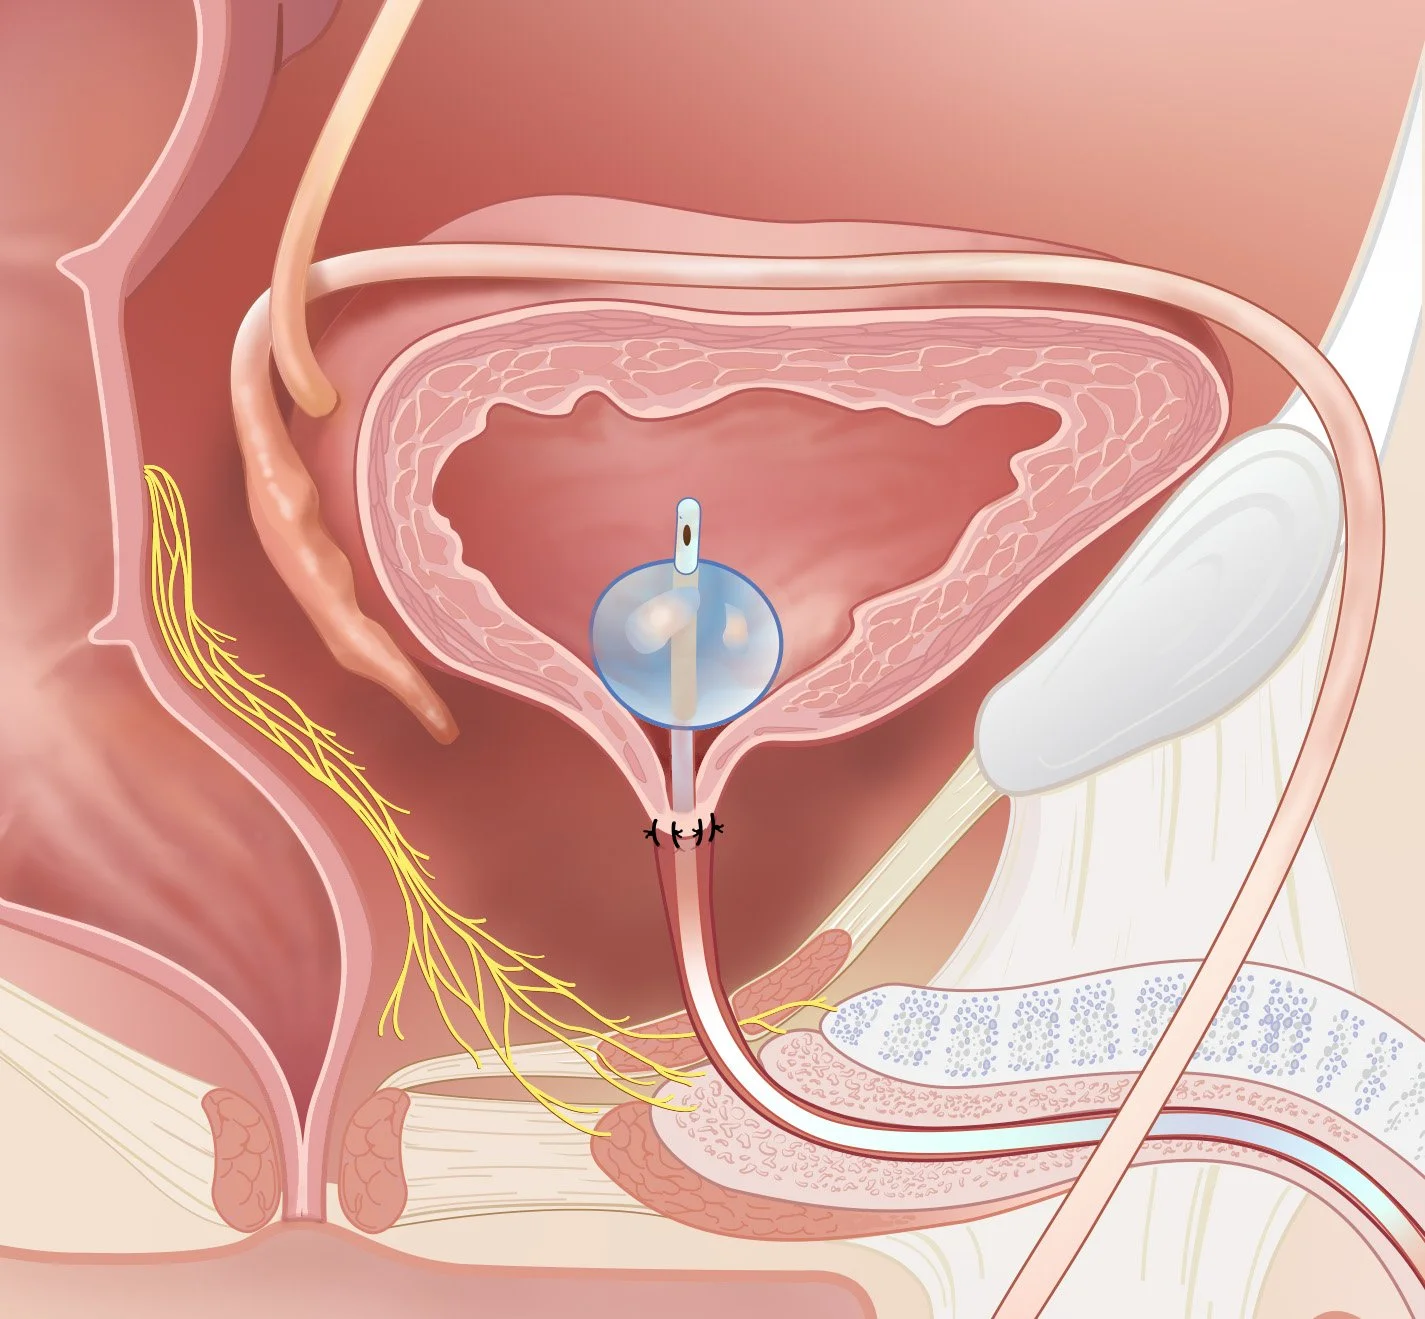

Informative, straightforward illustrations can help patients better understand their medical condition, treatments and procedures. Doctors and healthcare providers can use illustrations to communicate more effectively and reduce a patient’s anxiety about their condition or treatment.

Surgical illustrations visually depict operative techniques, surgical anatomy, and complex procedures. They are created with high anatomical accuracy and serve as a visual bridge between complex surgical knowledge and learners, clinicians, or patients.

Prostate Cancer Booklet

Created clear, accurate, and visually engaging medical illustrations for a patient education booklet on prostate cancer for a hospital system. The illustrations simplified complex anatomical and clinical concepts, helping patients better understand diagnosis, treatment options, and disease progression.

Client: Northwell Hospital System

Patient Education: Prostate Cancer